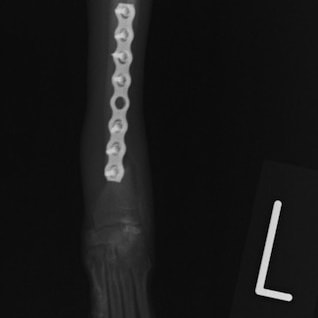

ペルシャ猫 11ヶ月齢 雄

他院にて左大腿骨遠位の成長板骨折(salter-harrisⅠ型)が認められており、治療相談を目的として来院。当院にて、キルシュナーワイヤーを用いたピンニングにより骨折部位の整復を行いました。術後の経過は良好で、現在も経過観察中です。

術後レントゲン